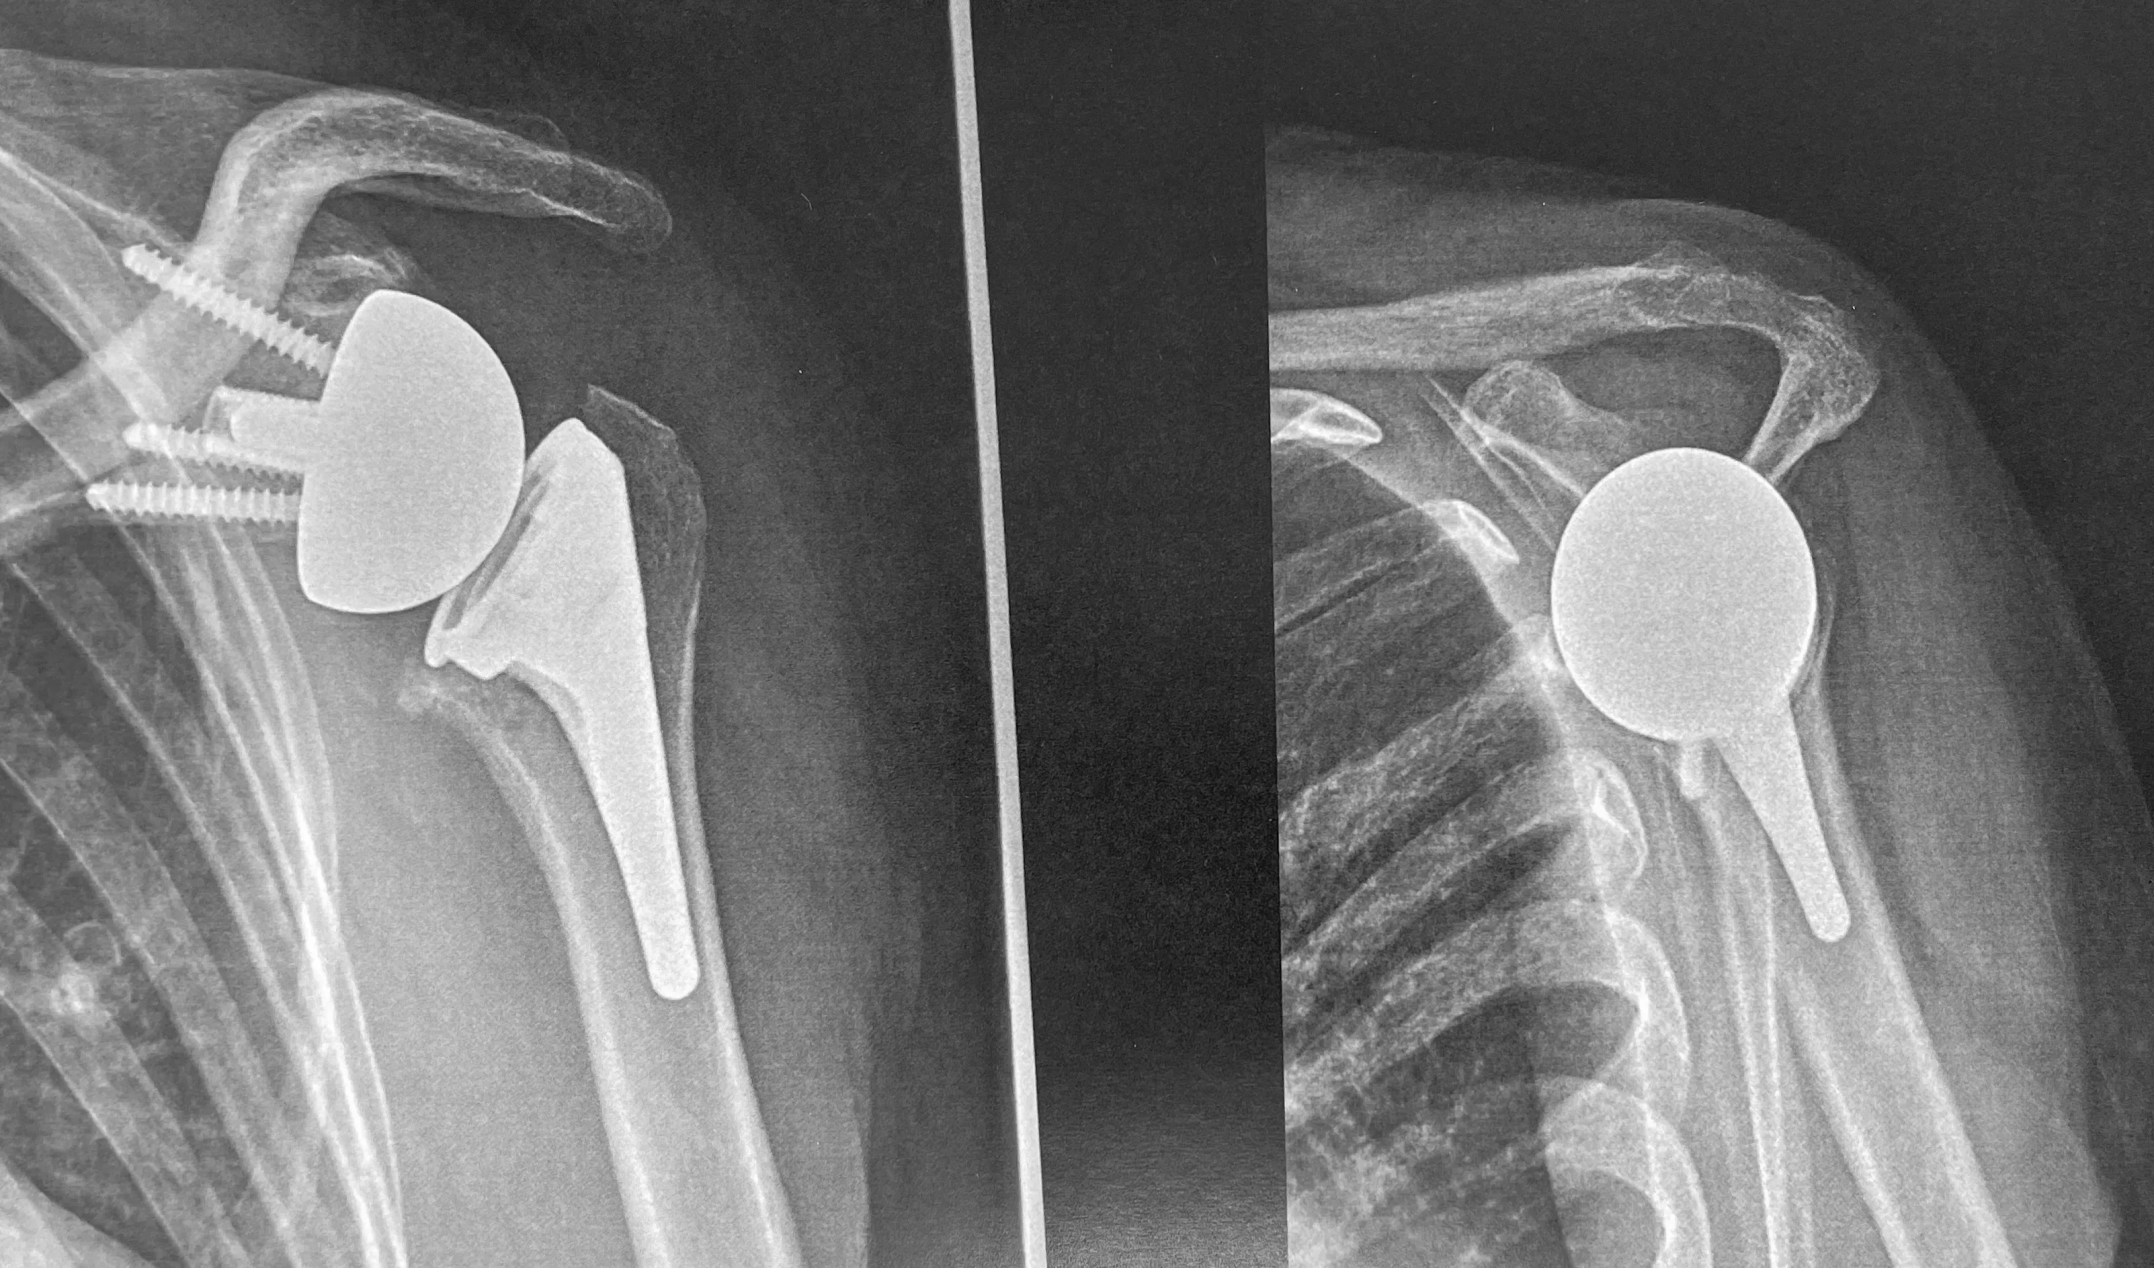

LES PROTHÈSES INVERSÉES DE L'ÉPAULE

Ce sont des prothèses qui sont utilisées lorsque les tendons de la coiffe des rotateurs sont rompus ou non fonctionnels.

Elles sont composées d'une tige humérale qui présente une cupule à sa partie supérieure et une pièce glénoïdienne qui a la forme d'une hémisphère. Le muscle deltoïde seul permettra l’élévation du bras.

Leur conception est dite "inversée" car la partie shérique est positionnée sur le versant glénoïdien contrairement à une épaule originelle. Cette architecture spécifique leur permet de pouvoir restaurer la fonction de l'épaule grâce à l'action du deltoïde qui devient le moteur principal de l'épaule.